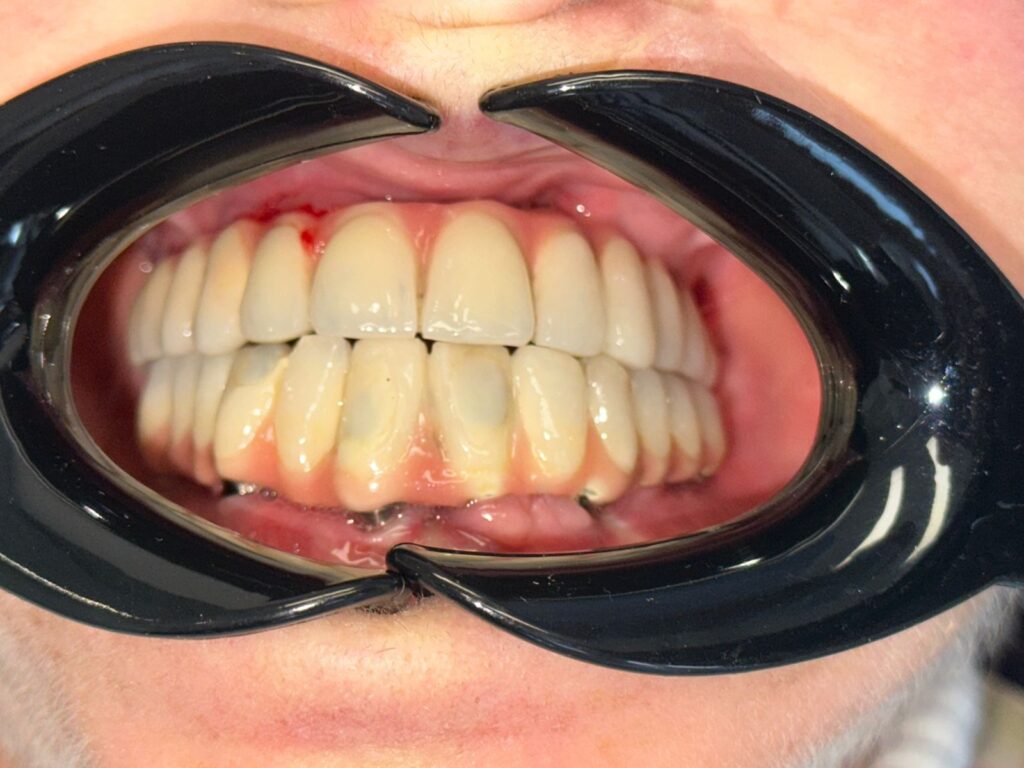

Ndërhyrja e dytë: rigjenerimi i indeve të buta

Pas stabilizimit të strukturave kockore, trajtimi vazhdoi me fazën e dytë kirurgjikale, e fokusuar në: Rigjenerimin e indeve të buta Përmirësimin e arkitekturës gingivale Krijimin e një mjedisi të shëndetshëm rreth implanteve Kjo fazë është shpesh e nënvlerësuar, por në raste të tilla komplekse, ajo është vendimtare për estetikën, funksionin dhe jetëgjatësinë e rehabilitimit.

Faza protetike: kur teknologjia dhe estetika bashkohen

Pas përfundimit të suksesshëm të fazave kirurgjikale, u kalua në vendosjen e punimit definitiv. Trajtimi përfundoi me: 24 kurora zirkoni full anatomi Të mbështetura mbi bar titani Dizajnuara për stabilitet maksimal dhe shpërndarje optimale të forcave Zirkoni u zgjodh për rezistencën e lartë, biokompatibilitetin dhe estetikën natyrale, ndërsa struktura e titanit siguroi qëndrueshmëri afatgjatë të implanteve dhe kurorave.